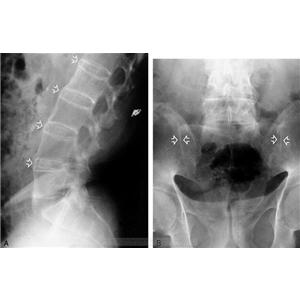

QZ16030094 姓名:陈先生 性别:男 年龄:32岁

- 病情

AS ①晚期 ②重度 病史:5年+

- 治疗

治疗后骶髂关节疼痛消失,腰椎前屈、背伸侧弯活动自如,膝关节无压痛感,复查血沉、C反应蛋白、等各项检查均已达到临床康复的标准。